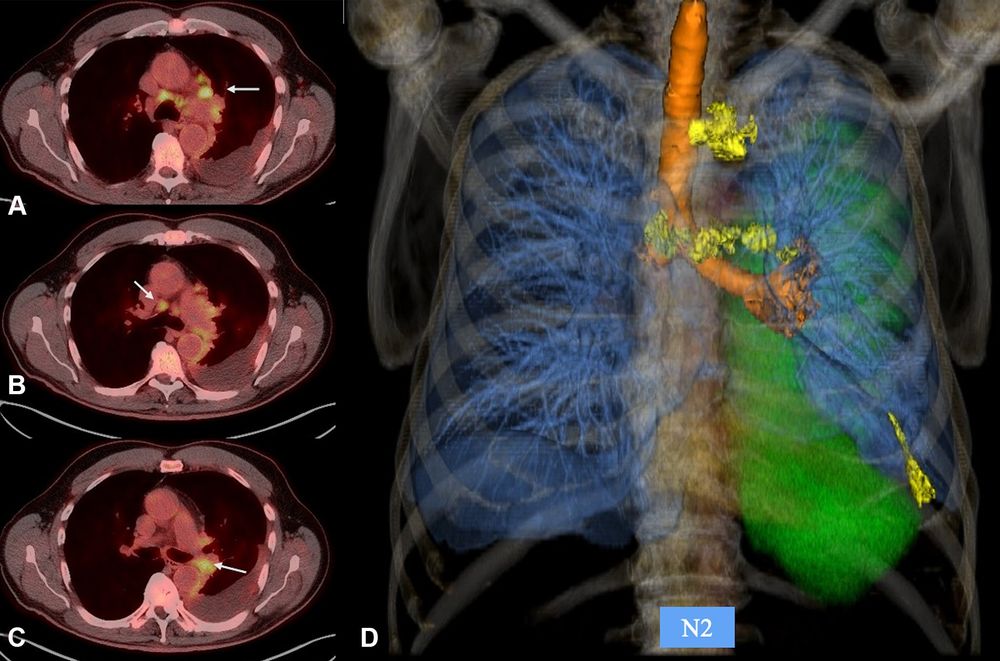

Pleural mesothelioma is a rare but aggressive cancer—with a median survival of only 9 months.

A new Radiology review details major updates to the TNM staging system, adding quantitative pleural measurements to improve accuracy, consistency, and patient care. https://bit.ly/42AeL2w

Pleural mesothelioma is a rare but aggressive cancer—with a median survival of only 9 months.

A new Radiology review details major updates to the TNM staging system, adding quantitative pleural measurements to improve accuracy, consistency, and patient care. https://bit.ly/42AeL2w